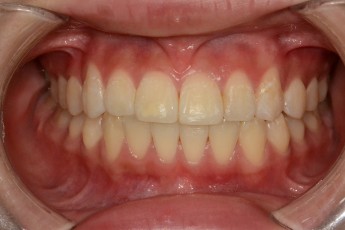

Before & After

- 덧니교정

Before

After